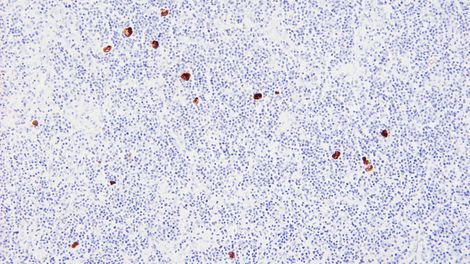

Reagent Provided EBER probe is a fluorescein-conjugated oligonucleotide probe (600 ng/mL) supplied in hybridization solution.

Specificity Latent EBV infection